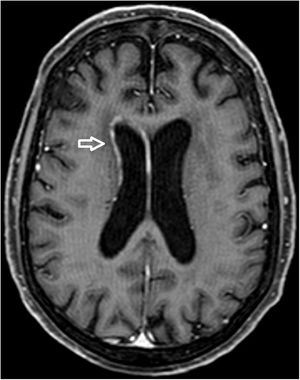

A 68-year-old woman with chronic bronchitis was admitted to the Intensive Care Unit at the start of the COVID-19 pandemic due to respiratory failure and bilateral lung infiltrates consistent with SARS-CoV-2 infection, though PCR testing proved negative on several occasions. During admission she suffered a progressive altered level of consciousness, requiring orotracheal intubation. Aspergillus lentulus was isolated from the bronchial aspirate. Lumbar puncture revealed: glucose 24 mg/dl, total proteins 133.6 mg/dl, leukocytes 136/µl and mononuclear cells > 95%. The brain CT scan showed no acute lesions and the brain MRI study revealed subependymal enhanced signal intensity around the frontal horn and atrioventricular zone of the lateral right ventricle (Figs. 1 and 2), with diffusion restriction in the apparent diffusion coefficient (ADC) study (Fig. 3). With the suspicion of fungal ventriculitis, PCR testing for Aspergillus spp. was performed in cerebrospinal fluid, with positive results.